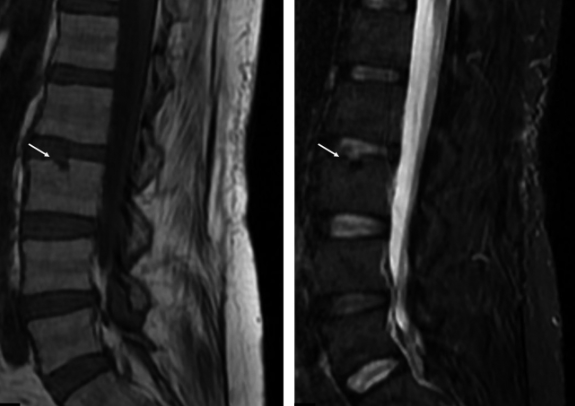

图一:LDH 患者 L4/5 在出现症状 5 个月后发生自发性消退

患者女,29 岁,因「右小腿疼痛并感觉异常」就诊,大小便正常。起始腰椎磁共振提示腰 L4/5 突出并椎管狭窄,神经根压迫严重(左图)。患者选择保守治疗,5 个月后复查 MRI(右图)发现突出的椎间盘自发性吸收了,并且临床症状基本缓解。